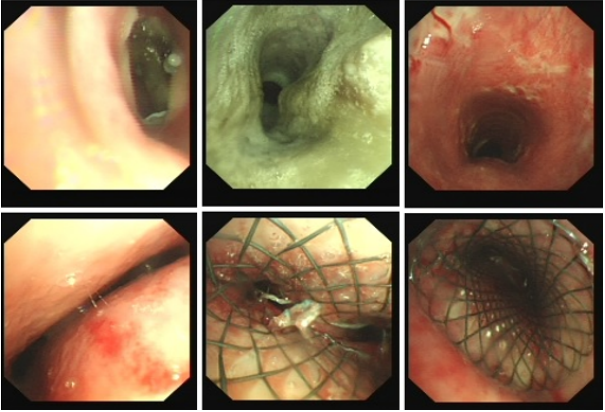

中心气道狭窄的治疗类技术主要是包括传统的外科手术和呼吸介入技术。传统手术创伤大,风险高。对于良性气道狭窄,术后存在吻合口瘢痕形成导致再狭窄可能。呼吸介入技术在良/恶性气道狭窄的治疗中发挥了非常重要的作用,包括热消融、冷冻、机械扩张、气道内近距离放射治疗、光动力治疗等技术(图2)。(1)慢起效消融技术:包括微波和冷冻(冻融),不适合气管重度腔内肿瘤开放气道治疗,因其可导致水肿,加重气道梗阻。冻融可以在吸高浓度氧时操作,简单、安全,不损伤支架,花费低,亦可用于装有起搏器的患者。(2)快起效消融技术:适合于较大的病变。主要包括:①激光:效率高(肿瘤切除金标准),设备贵、操作风险较大;②高频电:圈套器(效率高)适合于基底较窄的肿瘤,快捷安全,性价比高,吸氧低于40%;电刀、热活检钳、相对安全;③氩气刀(APC):止血效应安全高效,切除效率低;④冻切:效率高,操作风险较大(出血),凝血功能差,不宜选择。临床中需要根据患者的具体情况、手术特性和医生对操作技术的熟练度选择合适的热消融技术(表2)。气道支架包括硅酮支架、金属支架(覆膜支架,裸支架)。需要注意的是,硅酮支架贴壁性较差,不适合扭曲气道、不适用于锥形狭窄;重度外压型气道狭窄是气道支架治疗的绝对适应证;重度混合型狭窄适于覆膜支架置入治疗;良性气道狭窄严禁放置永久性金属支架。临床中需要参考CT或支气管镜检查选择合适的支架直径和长度,避免出现支架不稳、脱落或移位等情况。常用气管支架直径/长度为18、16 mm/40、60mm,左主支气管支架直径/长度为10、12 mm/30、40 mm,右主支气管支架直径/长度为12、14 mm/30、40 mm。笔者科室多选择软镜置入金属支架,在局麻及静脉镇静镇痛下(咪唑安定+芬太尼/舒芬太尼)能够顺利完成。大多数严重呼吸困难端坐呼吸的患者使用静脉镇静镇痛后均能平卧。